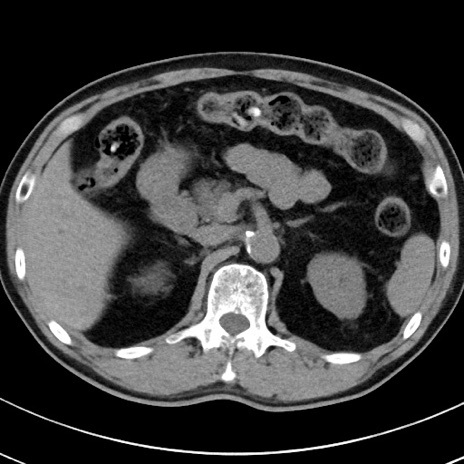

【腹部TIPS】症例29 参考症例 CT(横断像)

症例

70歳代男性